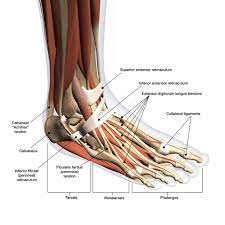

Lisfranc injury is an important topic. What is a lisfranc injury? Lisfranc injuries in the athlete. Sometimes, the injury is a simple dislocation (ligament injury), and sometimes a broken bone occurs. It is possible to sprain the lisfranc ligament, which does not require surgical intervention. Recovery can be slow and painful. A lisfranc injury is an injury to the ligaments that connect the bones of the midfoot and forefoot. A lisfranc joint injury happens when you damage bones or connective tissue called ligaments in the middle part of your foot. The lisfranc joint complex, named for the french surgeon who first described it in the 1800s, includes the five metatarsal bones along with the tendons and ligaments. The midfoot section refers to the. The usual mechanism is a direct blow or an indirect twisting force the lisfranc joint complex consists of the 5 tarsometatarsal joints that connect the forefoot and midfoot. A lisfranc injury describes an injury of the foot between the metatarsal and tarsal spaces. A lisfranc injury happens when the ligaments or bones in the middle of your foot are fractured, sprained or dislocated.

Sometimes, the injury is a simple dislocation (ligament injury), and sometimes a broken bone occurs. Injuries to the lisfranc joint most commonly occur in automobile accident victims, military personnel, runners, horseback riders, football players and participants of other contact sports. It is possible to sprain the lisfranc ligament, which does not require surgical intervention. A lisfranc injury or lisfranc sprain is an injury to the ligaments in the middle part of the foot, called the midfoot. The midfoot section refers to the. A lisfranc injury is a significant injury that involves the midfoot. Ebraheim's animated educational video describing lisfranc injury. The lisfranc joint complex, named for the french surgeon who first described it in the 1800s, includes the five metatarsal bones along with the tendons and ligaments.